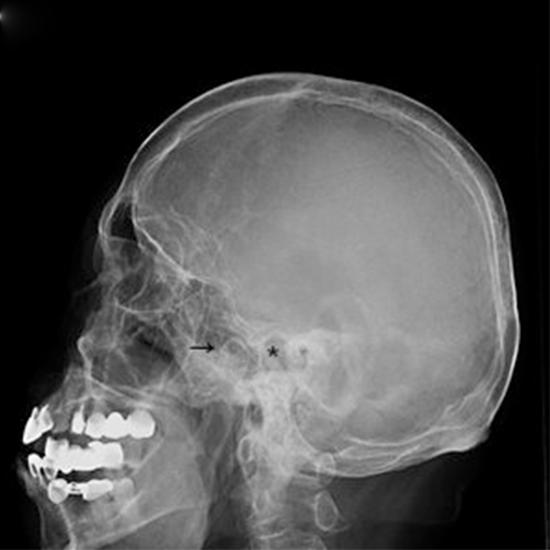

The bone that sits behind the ear and is a component of the skull's temporal bone is called the mastoid. This bone has spaces in it where air can get in. When there is an infection in the middle ear called mastoiditis, this area gets sick. The mastoid bone is examined from the side during the oblique view X-ray test.

The x-ray oblique view exam provides valuable mastoid information. It gives the following mastoid pathology results:

• Mastoid cellularity

• Cortical bone width

• Mastoid symmetry

• Determining whether or not the mastoid cavity is preserved

• Cholesteatoma information.